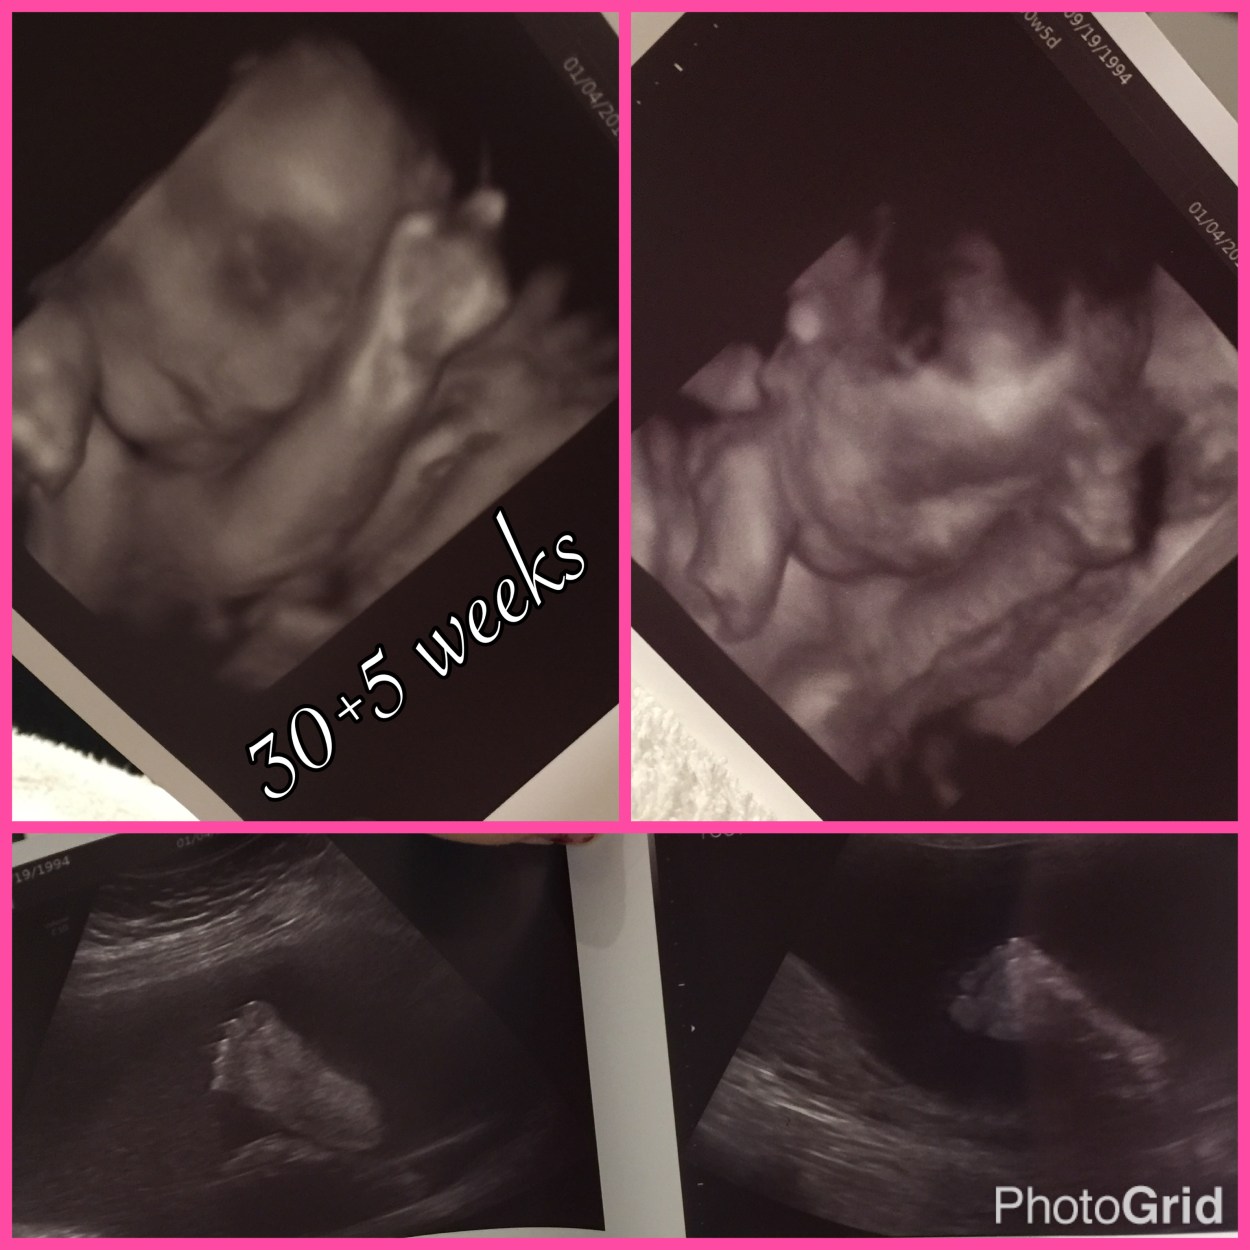

We went back to our room and started the ultrasound to see our baby again! Just going over every little part of her perfect body again and we stopped on her face and got some 3Ds of her. So overwhelming I just immediately had tears feeling my eyes. All I could think about was how perfect she looks and I’m going to have to say goodbye to her. I literally cannot even stand the thought of it.

Waiting for the doctor I just stared at all the pictures she printed off for us and just examined every little thing. She got pictures of her feet and they were seriously the sweetest thing. Soooo perfect.